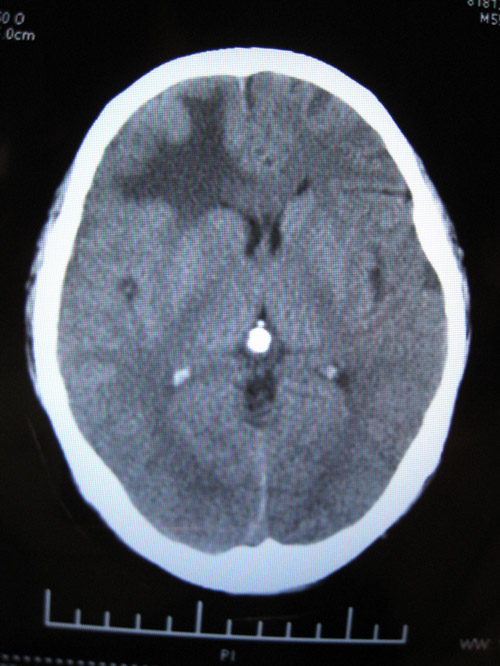

CTʱ¼ä2008-07-15 ÔçÉÏ9µãÖÓ

CT±¨¸æ

ÓÒ²à¶îÒ¶¼ûÇ·¹æÔòÍÅÆ¬ÉÔ¸ßÃܶÈÓ°£¬ÆäÖܱ߼ûƬ״µÍÃܶÈÓ°Ë®Ö×Ó°»·ÈÆ£¬±ß½çÇ·Ç壬¾Ö²¿¿É¼ûռλЧӦ£¬ÓÒ²à¶îò¨Ò¶ÄÔ¹µ±ädz£»ÓàÄÔʵÖÊÄÚδ¼ûÒì³£ÃܶÈÓ°£¬ÖÐÏßÏò×ó²àÒÆÎ»£¬Â¹Çδ¼ûÃ÷ÏÔ¹ÇÕÛ¡£

ÎÊÌâ²¹³ä£ºCTƬ2008-07-15 µÄÓ¡ÏóÊÇ£ºÓÒ²à¶îÒ¶ÄÔ´ìÁÑÉ˰éѪÖ×Ðγɣ¬¶ÔÕÕ08.07.09ƬѪÖ×ÉÔÎüÊÕ£¬Ë®Ö×Ïà·Â¡£